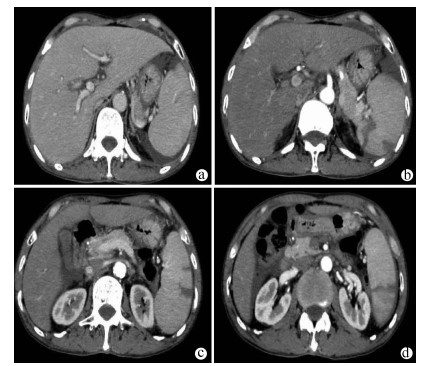

Jaundice and portal hypertension caused by hepatic epithelioid hemangioendothelioma: A case report

Ruihua ZHANG, Tingting QIN, Yueming SHAO, Yu ZHANG, Yang WANG, Xiaoyu WEN

2021, 37(7): 1662-1664. DOI: 10.3969/j.issn.1001-5256.2021.07.036

Abstract(1181) HTML (235) PDF (2873KB)(100)